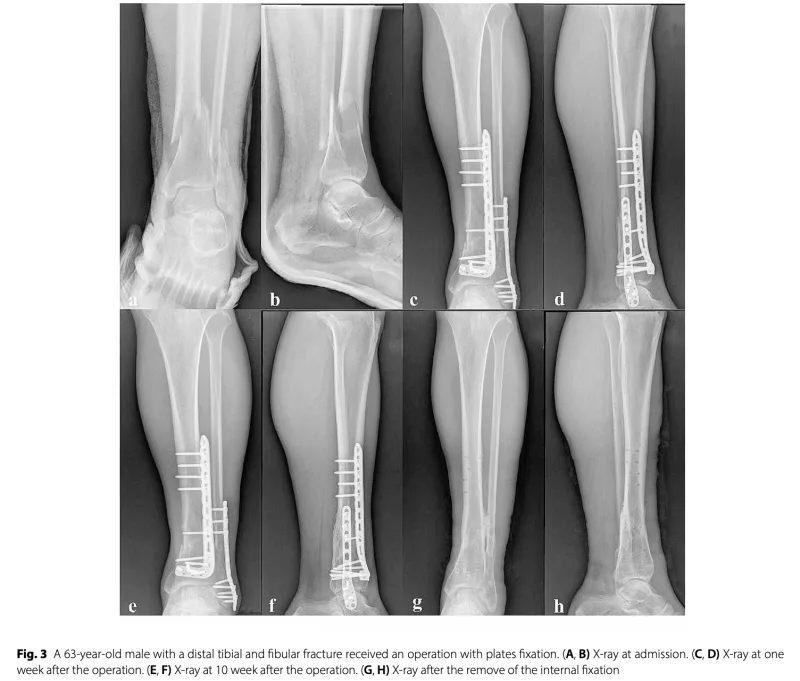

今日は, 脛骨遠位骨幹部骨折, 腓骨遠位骨幹部粉砕骨折の中高年患者さんの手術を執刀.

雪道で転倒受傷から2週間あまりが経過して, 腫れが引いたので, ようやく手術ができました.

脛骨, 腓骨ともにプレートとスクリューで固定.

予定通り, 2時間あまりで終了.